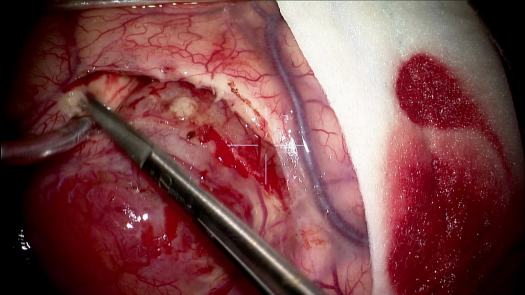

Resezione microchirurgica di tumore cerebrale (glioma alto grado cortico-sottocorticale) frontale dx